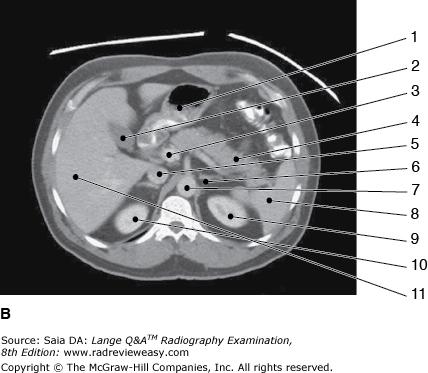

Which of the following statements is (are) true with regard to the two CT images seen below?

- Image A illustrates more superior structures.

- The images are sagittal reconstructions.

- The exam was performed without artificial contrast.

A 1 only

B 1 and 3 only

C 2 and 3 only

D 1, 2, and 3

-The figures are axial CT images of the abdomen with contrast. In Figure A, the liver (number 1 left lobe; number 6 right lobe; number 3 caudate lobe), barium-filled stomach (number 2), spleen (number 5), and aorta (number 4) are seen in image A. In Figure B, more inferior structures such as the inferior vena cava (number 5) and kidneys (number 9 and number 10) are seen.